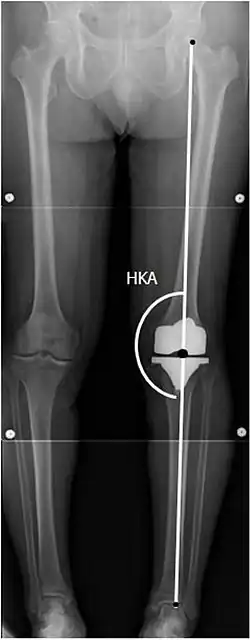

To indicate knee replacement in case of osteoarthritis, its radiographic classification and severity of symptoms both should be substantial. Such radiography should consist of weightbearing X-rays of both knees: AP, lateral, and 30 degrees of flexion. AP and lateral views may not show joint space narrowing, but the 30-degree flexion view is most sensitive for narrowing. Full-length projections also are used in order to adjust the prosthesis to provide a neutral angle for the distal lower extremity. Two angles used for this purpose are:

- Hip-knee-ankle angle (HKA),[11] which is an angle between the femoral mechanical axis and the center of the ankle joint.[12] It is normally between 1.0° and 1.5° of varus in adults.[13]

![HKA: Hip-knee-ankle angle, which is ideally between 3° varum to 3° valgum from a right angle.[62]](./X-ray_of_HKA_angle_with_knee_prosthesis.jpg)